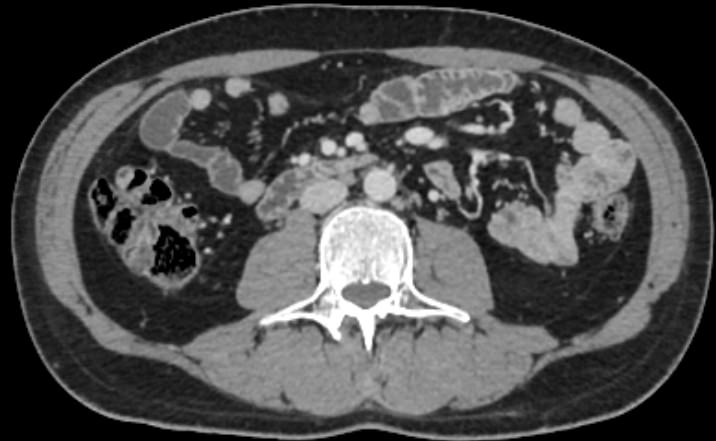

Для диагностики патологии нижней полой вены применяется высокоинформативный быстрый и неинвазивный (то есть не требующий вмешательства в организм пациента) метод исследования – мультиспиральная компьютерная томография (КТ-ангиография). КТ-ангиография позволяет диагностировать патологические изменения нижней полой вены на ранней стадии развития, когда лечение наиболее эффективно.

Метод компьютерной томографии основан на применении рентгеновского излучения. Источник излучения, расположенный в кольцевой части томографа, вращается вокруг зоны исследования и делает послойное сканирование со срезами толщиной от 0,5 мм. Для визуализации кровеносных сосудов обязательно используется контрастное усиление, которое усиливает контрастность сосудов на фоне окружающих тканей и позволяет увидеть патологические изменения на начальной стадии.

Для контрастирования используется йодсодержащий препарат, обладающий высокой рентгеноконтрастностью за счет способности поглощать рентгеновские лучи. Препарат вводится пациенту внутривенно во время исследования и позволяет диагностировать различную патологию нижней полой вены, включая аномалии развития, тромбозы, воспалительные изменения сосудистых стенок, опухолевые образования, прорастающие в нижнюю полую вену или сдавливающие ее извне.